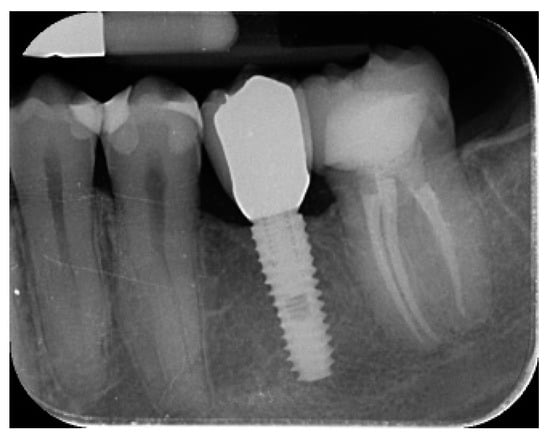

- Marginal bone level changes were assessed by digital periapical radiographs (Digora Optime; Soredex, Tuusula, Finland) using the parallel technique and commercially available film holders. Three time points were evaluated, at implant placement (baseline), immediately after the insertion of the restoration, and one year after loading. The averaged mesial and distal distances from the most coronal margin of the implant and the first bone-to-implant contact was measured to the nearest 0.01 mm and taken as the marginal bone level. The difference in levels between time points was taken as marginal bone loss (MBL).